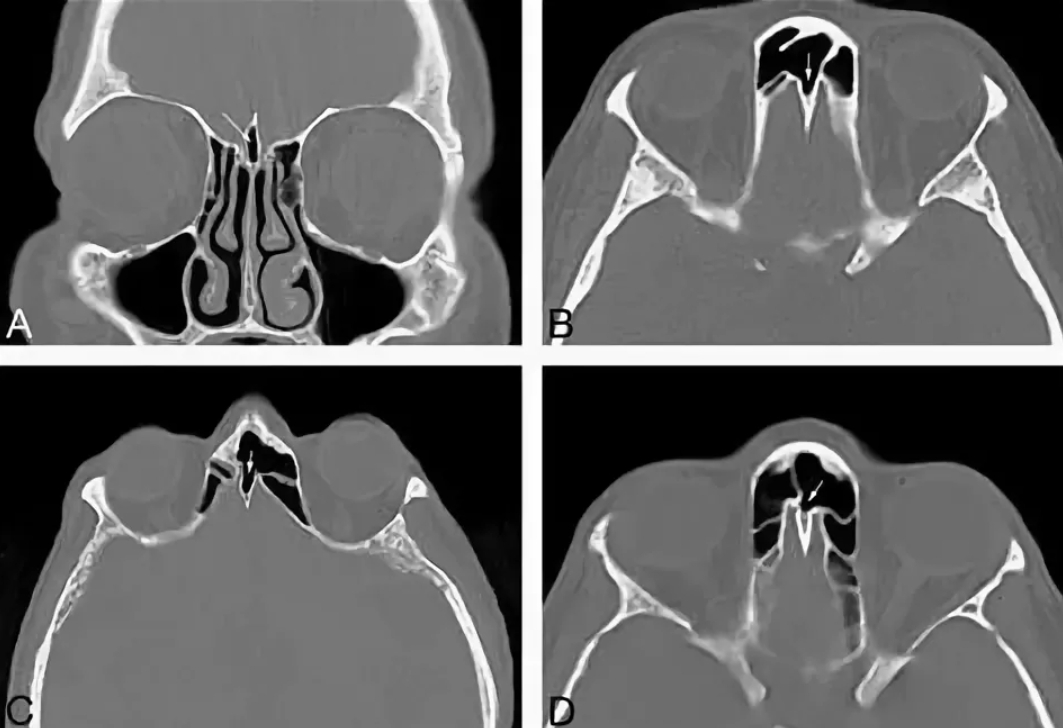

Компьютерная томография (КТ) пазух носа — это высокоточный метод лучевой диагностики, позволяющий получить детальные изображения околоносовых синусов, костных структур и мягких тканей. Процедура используется для выявления патологий, которые сложно обнаружить при стандартном рентгене или осмотре. Разберемся, в каких случаях она необходима и как проводится.

- Точно оценить состояние костных стенок пазух и их пневматизацию;

- Обнаружить даже мелкие образования (кисты, полипы) размером от 1–2 мм;

- Дифференцировать воспалительные процессы от опухолевых;

- Наличие жидкости, гноя или утолщений слизистой оболочки;

- Состояние соустий (отверстий, соединяющих пазухи с носовой полостью);

- Деформации костных структур;

- Признаки опухолей или метастазов.